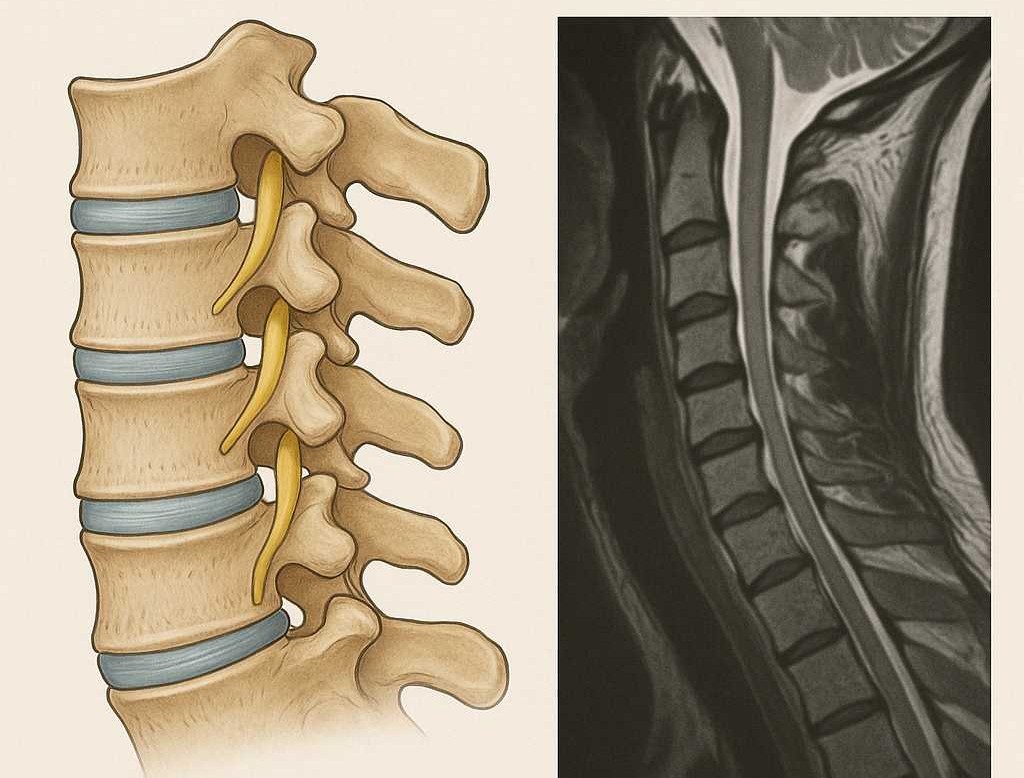

MRI (ام آر آی): بهترین روش برای دیدن کاهش آب دیسک و میزان آسیب آن است. در MRI، دیسک دهیدره به رنگ تیرهتر نسبت به دیسک سالم دیده میشود.

| در MRI | کاهش شدت سیگنال (رنگ تیرهتر دیسک) | بیرونزدگی واضح دیسک و فشار بر عصب |